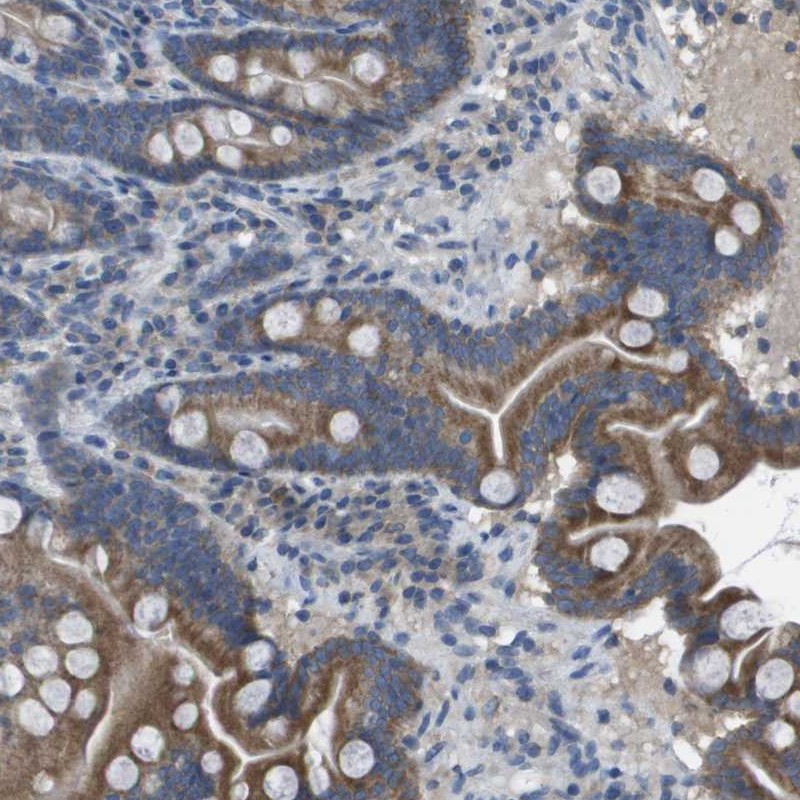

Immunohistochemical staining of human duodenum shows moderate cytoplasmic positivity in glandular cells.